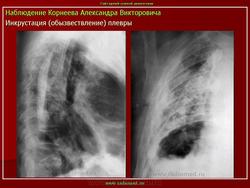

Обызвествления плевры